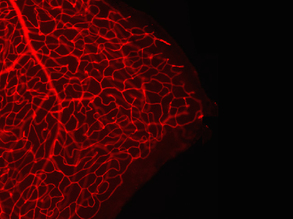

Red Eye